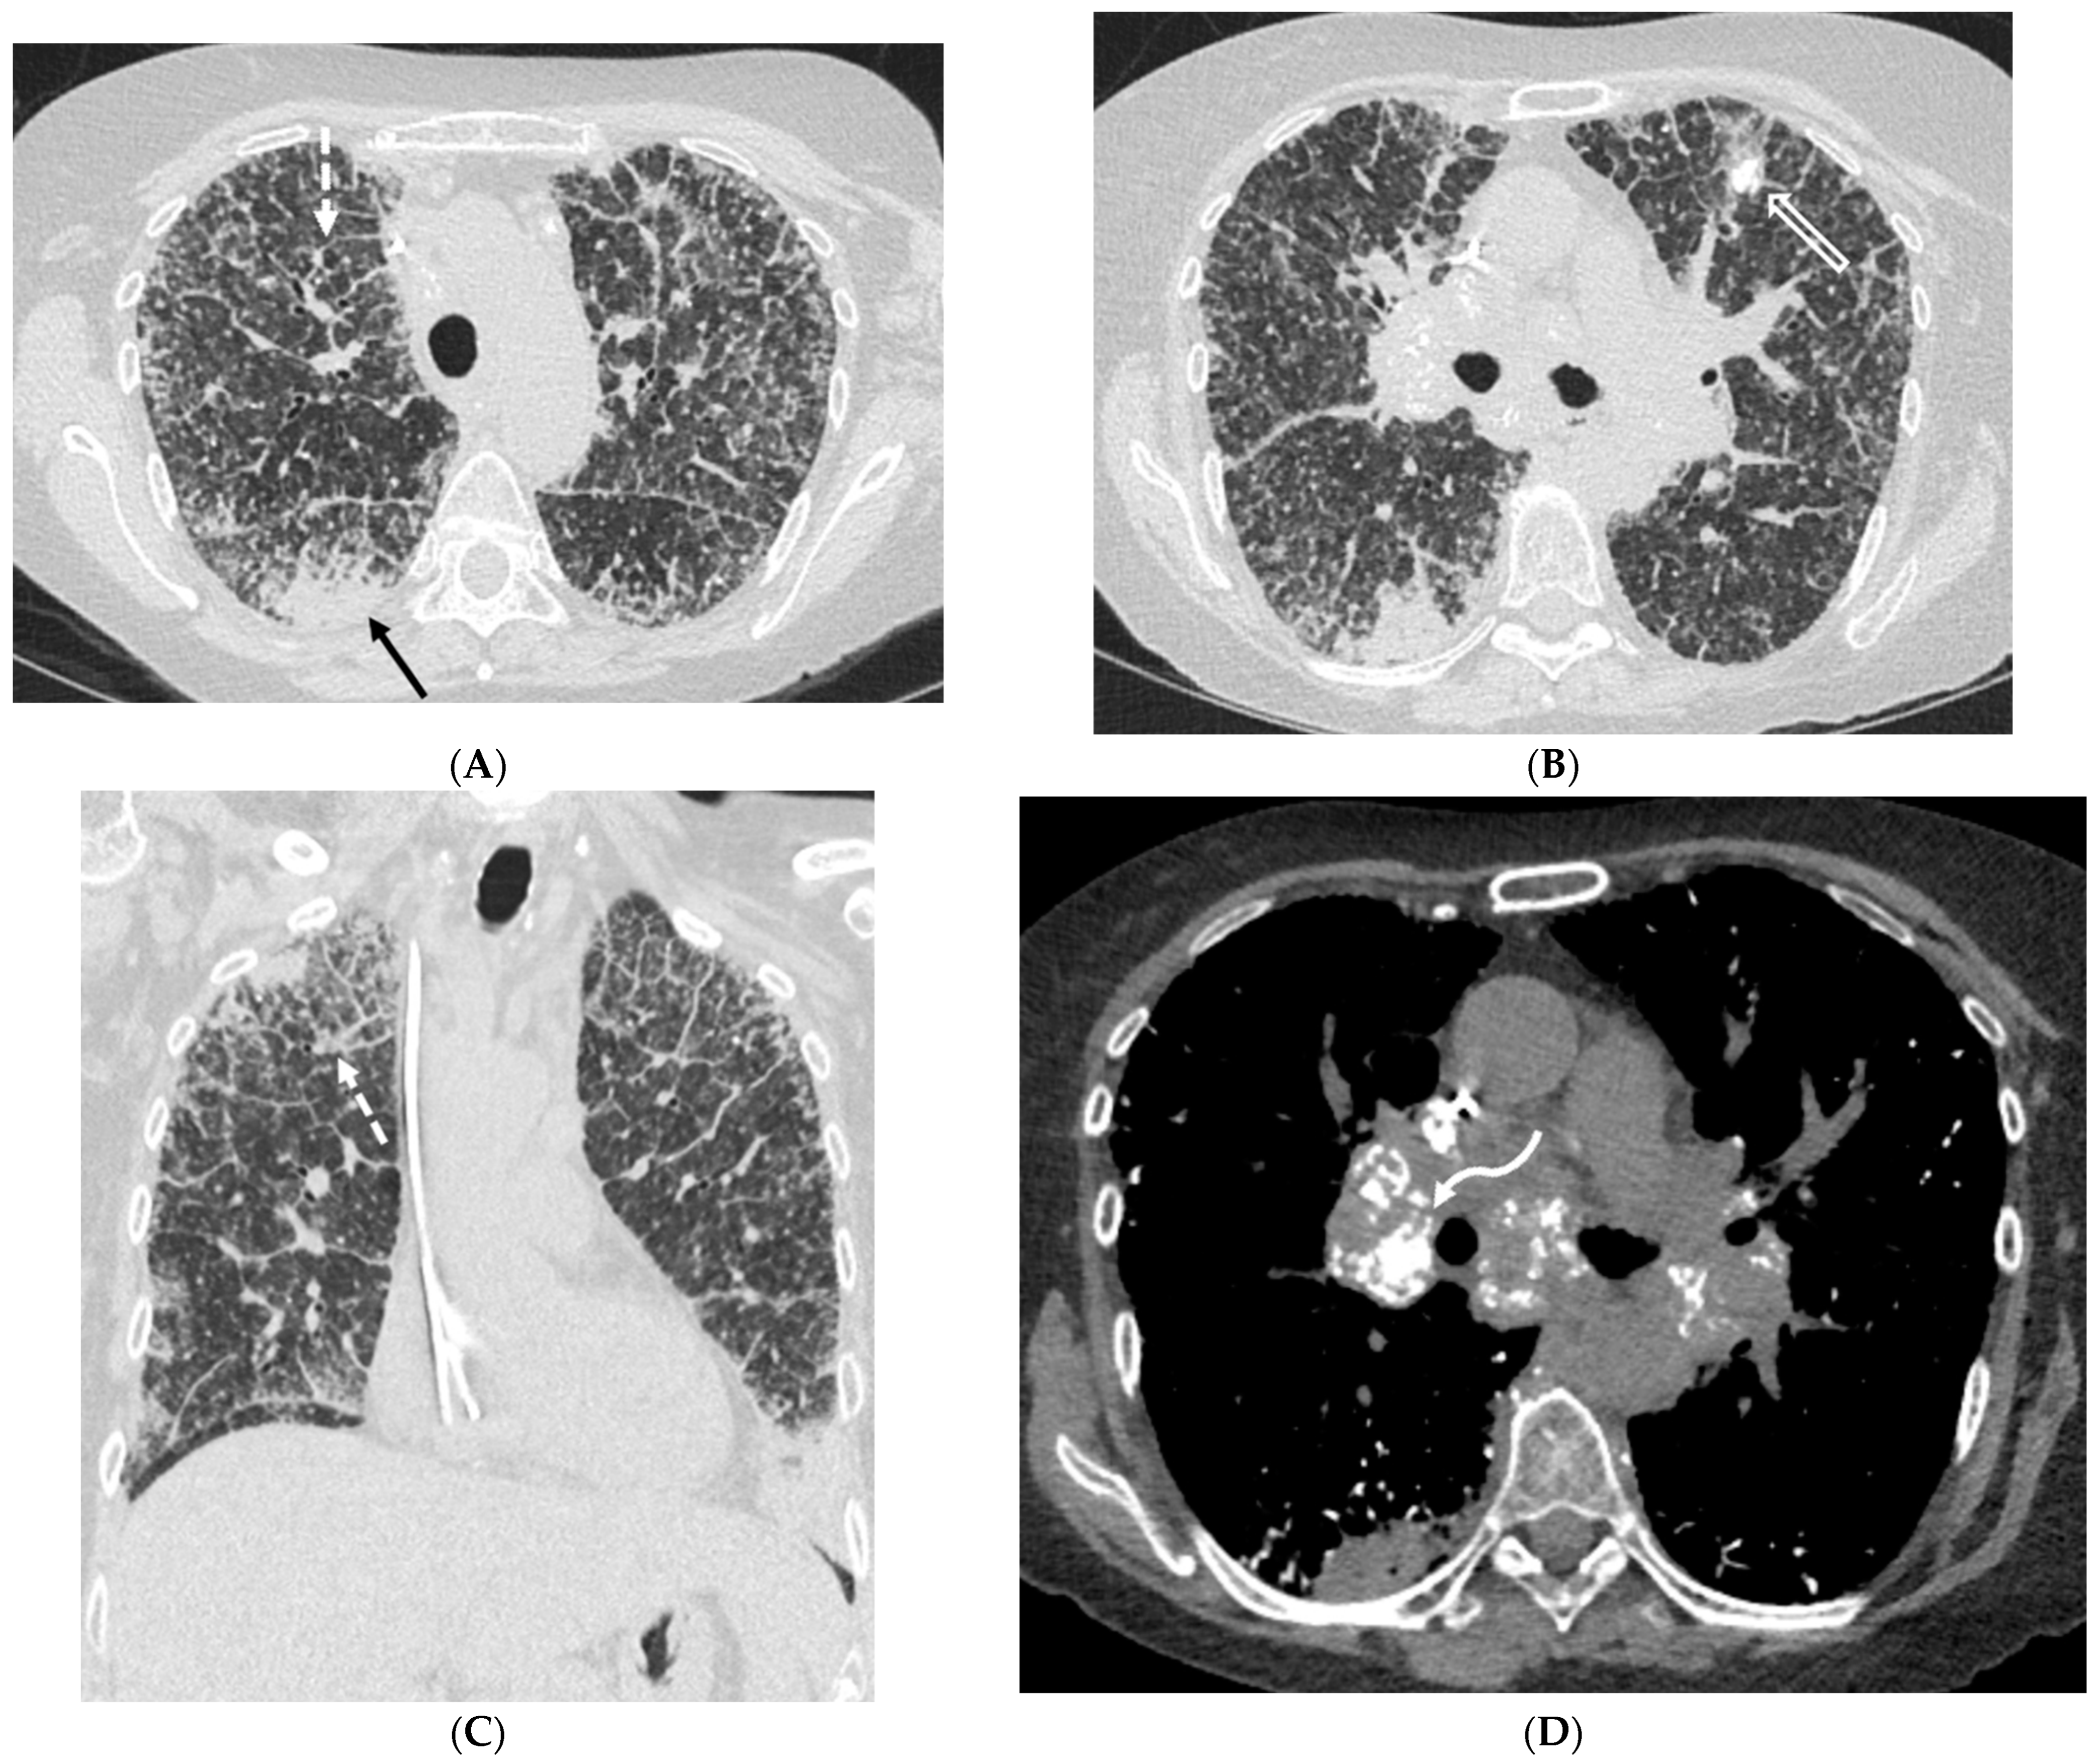

6.2. Pulmonary Alveolar Proteinosis (PAP)

6.3. Amyloidosis